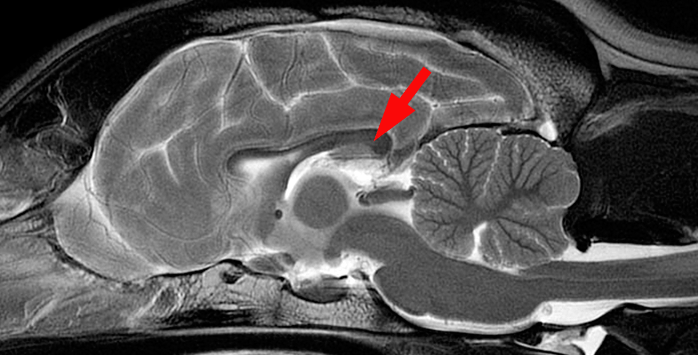

Sezione mediana dell’encefalo di cane in risonanza magnetica strutturale (sMRI) – la freccia rossa indica il corpo calloso

Il corpo calloso si trova al fondo della fessura longitudinale dell’encefalo (scissura interemisferica). È un robusto fascio di sostanza bianca e consiste di una parte principale detta tronco, di un’estremità posteriore (splenio), di un’estremità anteriore (ginocchio) e di un sottile rostro che si estende dal ginocchio fino alla commessura anteriore. Prova a identificare queste parti del corpo calloso nell’immagine in sMRI in alto.